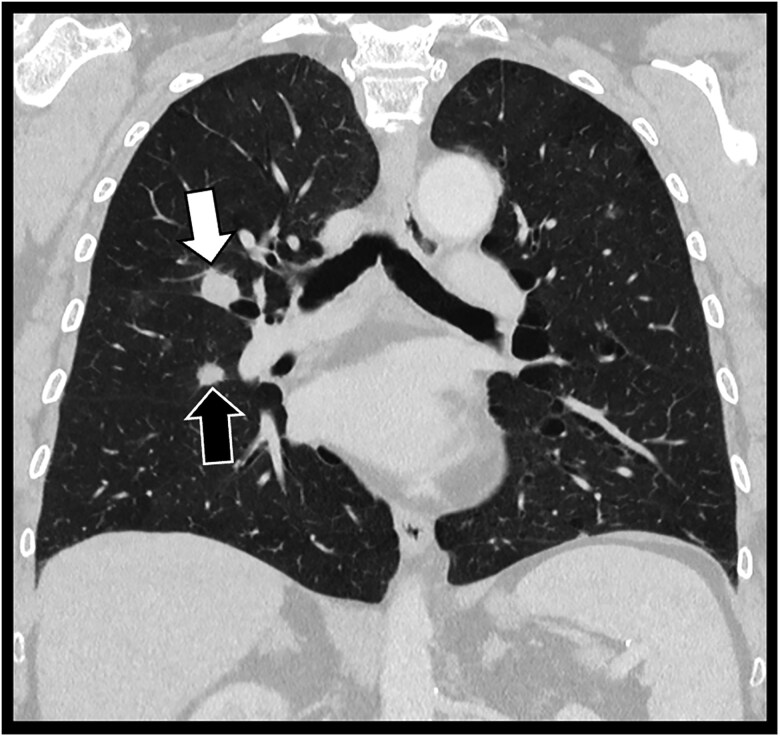

Abstract Image